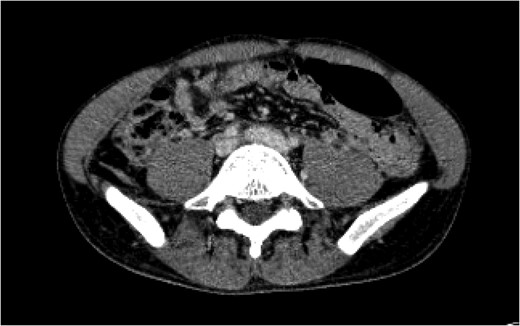

The visceral arteriogram demonstrated extravasation from the right adrenal artery and superior pole of the kidney, both of which were embolized with microcoils. Post-embolization angiography demonstrated no further evidence of active extravasation. There was no injury to the aortic bifurcation. A venogram was then performed, which demonstrated a 2.8 cm pseudoaneurysm arising from the proximal portion of the left common iliac vein with involvement of the base of the IVC without active extravasation. There was no involvement of the right common iliac vein. The patient continued to be hemodynamically stable so the decision was made to observe him. After an initial hemoglobin drop from 14.3 to 6.9 g/dL within the first 48 h, he stabilized between 8 and 9 g/dL after two units of packed red blood cell transfusion and then remained hemodynamically stable throughout his stay. He was initiated on aspirin and therapeutic heparin for his carotid dissection on hospital Day 2 and underwent a cerebral angiogram and right internal carotid stent placement on hospital Day 14. A CT venogram on hospital Day 16 demonstrated a decrease in size of the pseudoaneurysm, and a stable prevertebral and pelvic retroperitoneal hematoma (Fig.

3). These were managed conservatively as the patient’s hemoglobin and hemodynamics were stable. Given the concern for intraluminal thrombus extension from the pseudoaneurysm, the decision was made to continue therapeutic anticoagulation. He was bridged to warfarin on hospital Day 17 and discharged to a rehabilitation facility on hospital Day 20 on therapeutic anticoagulation and full dose aspirin.

Figure 3:

A CT angiogram of the chest with and without contrast on Day 16 showed resolution of the pseudoaneurysm in the proximal left common iliac vein with clear flow at the IVC bifurcation.